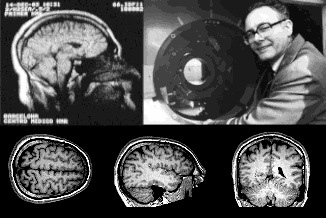

Первые атаки рентгеновскими лучами и ультразвуком отражены черепом

В 1895 году немецкий физик Вильгельм Конрад Рентген на две недели заперся в своей лаборатории, чтобы описать свойства случайно обнаруженных им X-лучей, названных впоследствии рентгеновскими. Излучение сильно поглощалось костной тканью, и уже год спустя врачи использовали рентгенографию черепа для диагностики переломов, смещений и инородных тел. В 1901 году В. Рентген был удостоен Нобелевской премии по физике, а в 1918 — в России создана первая рентгенологическая клиника. Однако небольшая доля рентгеновских лучей, проходящих через кости черепа, плохо поглощается цереброспинальной жидкостью и мозговыми тканями (рис. 17А). Чтобы хоть что-то рассмотреть внутри черепа, необходимо было придать мозговым структурам контраст. В 1918–19 гг. американский нейрохирург Уолтер Денди предложил для этого воздушное контрастирование (рис. 17Б). Через иглу-проводник воздух вводили в пространство с цереброспинальной жидкостью, омывающей спинной и головной мозг (туда несложно и безопасно попасть с помощью прокола в поясничной области — эта процедура называется люмбальной пункцией). Воздух контрастировал мозговые желудочки (вентрикулография) и субарахноидальные пространства вокруг мозга (пневмоэнцефалография). Однако процедура неизбежно сопровождалась сильной головной болью, поэтому требовала выдержки не только от врача, но и от пациента. Тем не менее, десятилетиями только эти методы позволяли приблизиться к визуализации мозга — к счастью, сейчас они не используются [68].

В 1927 году португальский невролог Антониу Эгаш Мониш предложил вводить йодсодержащее рентгеноконтрастное вещество в мозговые сосуды и разработал метод церебральной ангиографии, который до сих пор активно используют сосудистые нейрохирурги (рис. 17В) [69]. Однако Нобелевскую премию Мониш получил не за этот метод, а за разработку лоботомии — запрещенного в настоящий момент метода отсечения трактов лобных долей от остальных частей мозга у душевнобольных пациентов [70], о котором мы еще поговорим в следующей главе.

Очень скоро в визуализацию мозга вмешались химики. В 1973 году американский химик Пол Лотербур предложил использовать явление ядерного магнитного резонанса (ЯМР), активно применяемого в расшифровке химической структуры молекул, для построения цифровых изображений. Ряд ученых, в том числе отечественных, уже высказывали эту идею ранее, но по иронии судьбы им всем, включая Лютербура, не выделяли государственного финансирования на разработку прибора, настолько фантастически-невозможным казалось воплощение идеи. Однако Лотербуру удалось впервые получить на своем приборе ЯМР-изображения (рис. 20А). Далее английский физик Питер Мэнсфилд усовершенствовал математические алгоритмы преобразования ЯМР-спектров в цифровое изображение. Мэнсфилд «не пощадил живота своего» — за полчаса он просканировал на приборе свою брюшную полость, чтобы убедить всех, что его метод эффективен и безопасен. С 1982 г. началось коммерческое производство ЯМР-томографов. После аварии на Чернобыльской атомной электростанции в 1986 г. ЯМР-томографы стали называть просто магнитно-резонансными томографами или МРТ, чтобы не пугать людей — ведь метод не дает лучевой нагрузки, в отличие от КТ (рис. 20Б). В 2003 году П. Лотербуру и П. Мэнсфилду была присуждена Нобелевская премия [73].